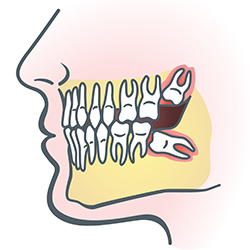

Wisdom teeth are molars found in the very back of your mouth. These teeth usually appear in late teens or early twenties but may become impacted (fail to erupt) due to lack of room in the jaw or angle of entry. When a wisdom tooth is impacted, it may need to be removed. If it is not removed, you may develop gum tenderness, swelling, or even severe pain. Impacted wisdom teeth that are partially or fully erupted tend to be quite difficult to clean and are susceptible to tooth decay, recurring infections, and even gum disease.

Wisdom teeth are typically removed in the late teens or early twenties because there is a greater chance that the teeth's roots have not fully formed and the bone surrounding the teeth is less dense. These two factors can make extraction easier, as well as making the recovery time much shorter.

In order to remove a wisdom tooth, your dentist first needs to numb the area around the tooth with a local anesthetic. Because the impacted tooth may still be under the gums and imbedded in your jaw bone, your dentist will need to remove a portion of the covering bone to extract the tooth. In order to minimize the amount of bone that is removed with the tooth, your dentist will often "section" your wisdom tooth so that each piece can be removed through a small opening in the bone. Once your wisdom teeth have been extracted, the healing process begins. Healing time varies depending on the degree of difficulty related to the extraction. Your dentist will share with you what to expect and provide instructions for a comfortable, efficient healing process.